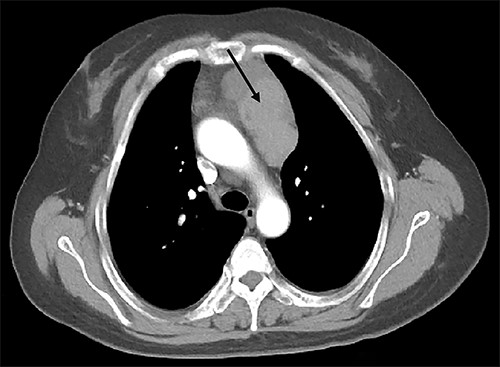

A 39-year-old Chinese female was diagnosed with a pituitary tumor at age 18 when she noticed aberrant growth development. Throughout the years, she developed PHPT, gastrinoma and bilateral adrenal hyperplasia. She was referred to our hospital for further evaluation to confirm the diagnosis of MEN1. Enhanced computed tomography (CT) demonstrated a 7.8-cm by 3.5-cm irregular anterior mediastinal solid-cystic mass within the thymic region (Fig. 1). The lesion was highly suspicious for thymic neoplasm radiologically. The patient subsequently underwent a video-assisted thoracoscopic thymectomy under general anesthesia. No tumor invasion to the pericardium and lung was observed, and the tumor was completely removed. Histopathology examination revealed WHO Type AB thymoma (Masaoka Stage I) (Fig. 2). Following surgery, annual screening showed no evidence of local recurrence or distant metastasis.

Enhanced CT scan of the chest revealed an anterior mediastinal tumor (black arrow).